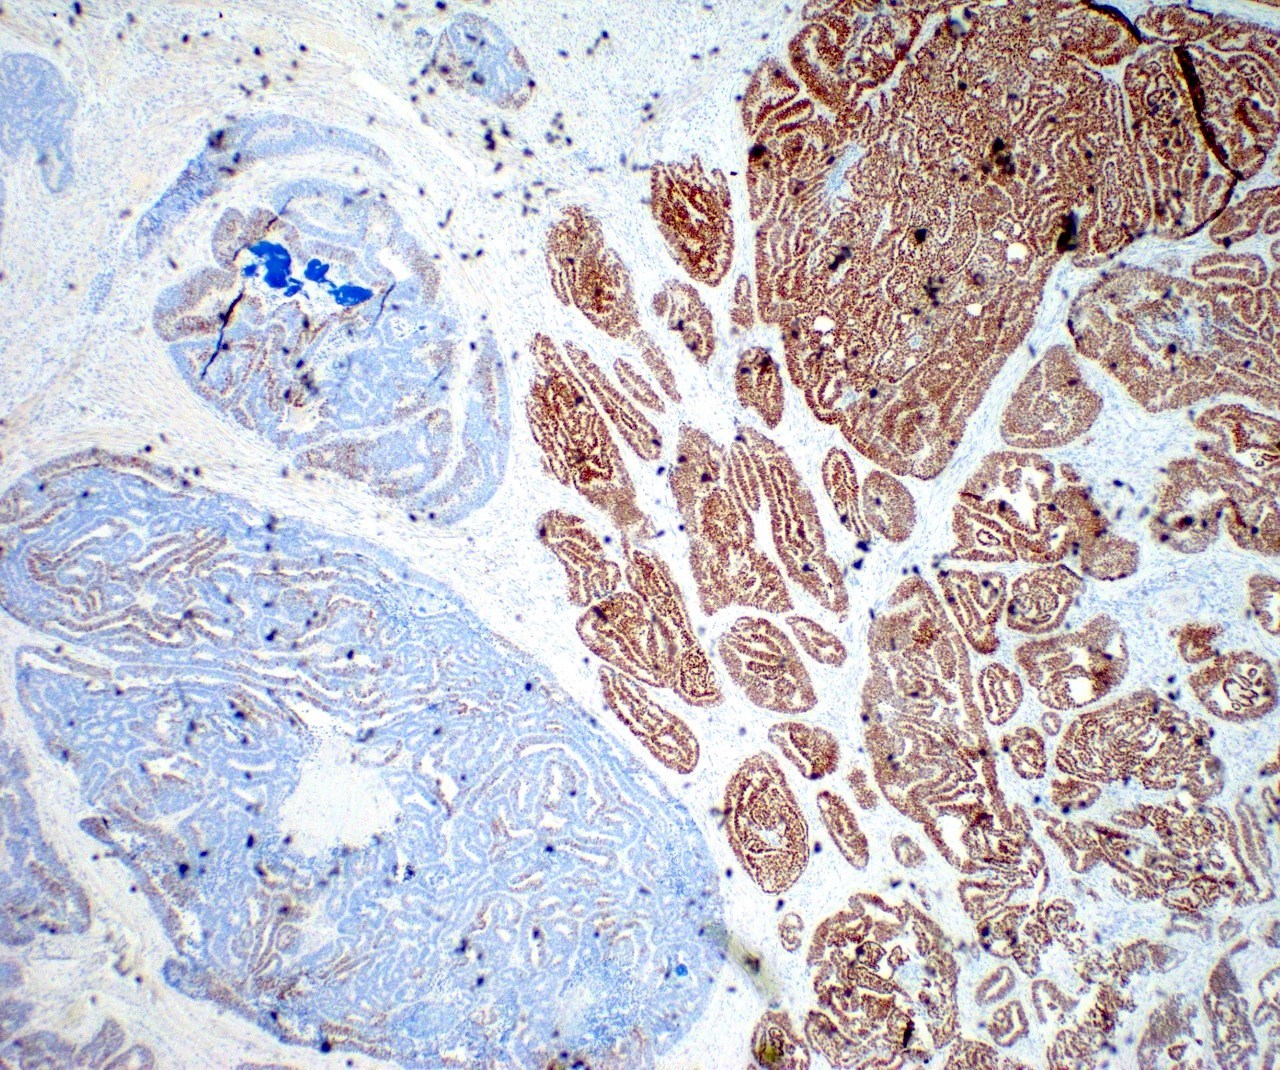

Microscopic (histologic) images

Contributed by Daniel Graham, M.D., Adele Wong, M.B., B.Ch., B.A.O. and Lucy Ma, M.D.

- GATA3 and TTF1: focal or diffuse with inverse staining pattern described in several studies in the most recent WHO classification; cells positive for GATA3 are negative for TTF1 and vice versa (Am J Surg Pathol 2018;42:1596)

Negative stains

- ER

- PR (more reliable negative marker than ER)

- Calretinin (usually negative may be focally positive)